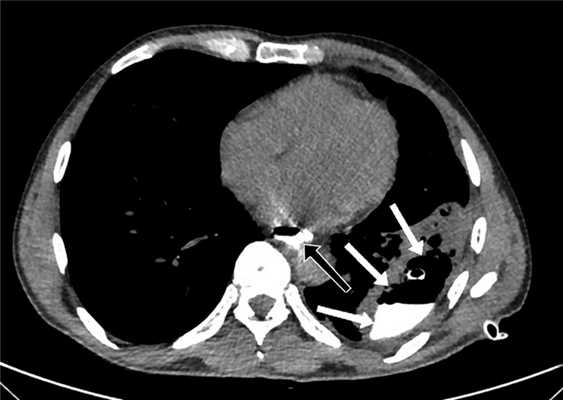

Для определения размера и локализации затеков в средостении, плевральных или брюшной полостях и динамики их уменьшения пациентам выполнена КТ с пероральным контрастированием (рис. 2). Рис. 2. Компьютерная томограмма пациента после низведения желудка, проксимальной резекции желудка с резекцией эзофагогастроанастомоза и еюногастропластики. Желтой стрелкой указана зона несостоятельности анастомоза, красными — область затека контрастного препарата.